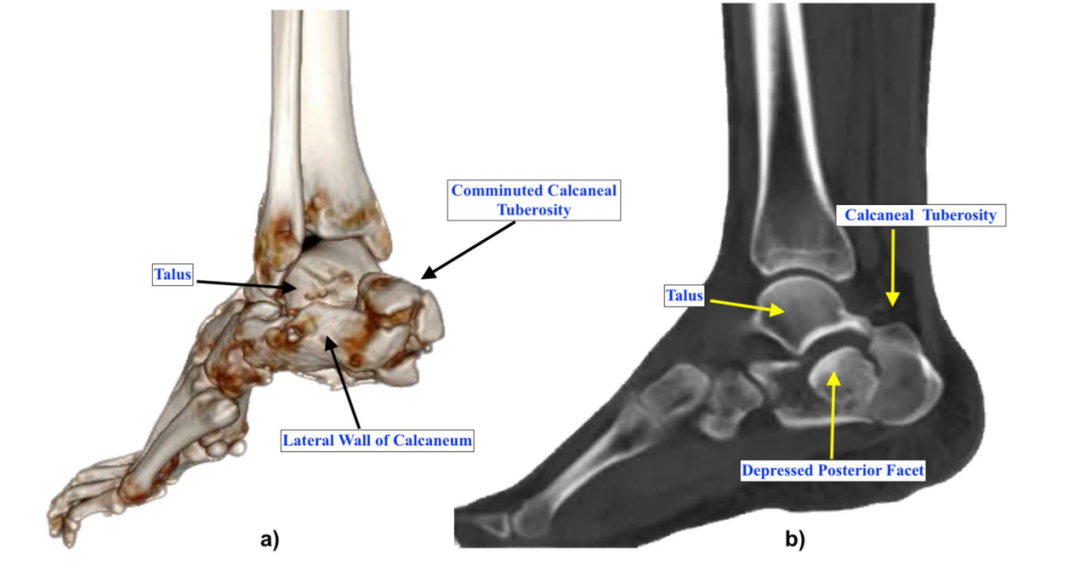

▲图示 a-b 克氏针固定复位的透视侧位片;c 跟骨轴向横截面示意图,显示克氏针从外侧穿入并将骨折块与距骨固定。

▲图示 a-b 后关节面复位固定后,跟骨结节复位前后的侧位透视片;c 克氏针固定后的侧位透视片;d 跟骨轴向横截面示意图,显示克氏针跨距下关节固定;e 手术切口缝合后的临床照片。